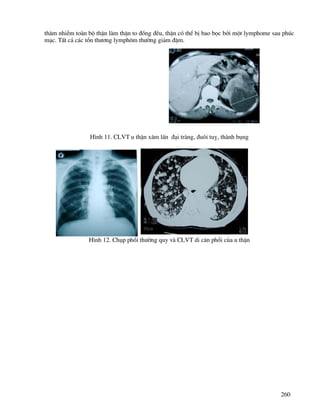

th−êng vÒ sè l−îng, vÞ trÝ cña thËn ( thËn sa, l¹c chç), thËn dÝnh nhau, c¸c bÖnh lý trªn thËn bÊt

th−êng (h×nh 22,23,24,25,26 27).

H×nh 22.ThËn ®«i trªn CLVT

H×nh 23. ThËn dÝnh nhau tr−íc c¸nh chËu ph¶i

trªn UIV vµ CLVT

H×nh 24. H×nh ¶nh CLVT thËn trong tiÓu khung, sái bÓ thËn

H×nh 25. H×nh ¶nh CLVT thËn l¹c chç trong lång ngùc ø n−íc, cã sái bÓ thËn

H×nh 26. H×nh ¶nh thËn mãng ngùa dÝnh nhau b»ng nhu m«

H×nh 27. Siªu ©m hÑp vÞ trÝ nèi bÓ thËn- niÖu qu¶n tr¸i vµ UIV, CLVT hÑp vÞ trÝ nèi bÓ thËn niÖu

qu¶n ph¶i